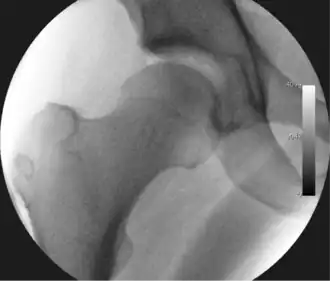

Intraoperative fluoroscopic image during an arthroscopic resection of a cam lesion of the femur. The upper instrument is the arthroscope (viewing device), while the lower is the high-speed burr used for reshaping the bone.

The next step is to insert a fine needle under x-ray guidance into the hip joint. This breaks the 'suction seal' of the joint and allows further distraction if necessary (see fig 4). The surgeon wishes to see the ball move out the socket by approximately 1 cm, so that access to the hip joint can be achieved with minimal risk of damage to the joint surfaces. Most surgeons will inject fluid into the joint at this stage, again to ensure that there is enough space between the ball and socket for safe instrument access. This needle is then removed. The next step is placement of the 'portals', or the small holes made to pass instruments into the joint. This is achieved by again passing a fresh hollow needle into the joint under x-ray control, usually in a slightly different position. The reason for this is so the surgeon can ensure that the needle, and subsequent cannulae do not penetrate and damage the acetabular labrum or cartilage joint surfaces (see fig. 5). Again, surgeons will have their own preferences as to their preferred placement. Through this hollow needle, a long thin flexible guide wire is passed into the joint, and the needle is removed over it, leaving the guide wire in situ. A small cut in the skin is made around the wire, to allow for larger cannulae to be placed over the wire through the portal. The wire therefore guides the larger cannulae into the joint. The most common external diameters of cannulae used are between 4.5 and 5.5 mm. Once the surgeon is satisfied that the cannula is in the correct position, by a combination of feel and x-ray guidance, the guide wire can be withdrawn. Once the first portal is correctly placed, any further portals may be created once the camera is in position, to ensure that they are placed with minimal risk to the joint surfaces. This process can be repeated to gain as many points of entry to the hip joint as the surgeon requires, normally between two and four. Certain of these entry points will be used for the viewing arthroscope and others for operating instruments.

Standard arthroscopic treatment of symptomatic cam FAI involves debridement (resection) or repair of any labral [10] and chondral injuries [11] in the central compartment of the hip, and subsequent reshaping of the head-neck junction of the upper femur (osteochondroplasty) in the peripheral compartment [12][13] using high-speed motorised burrs that are similar in design to a dentist's drill (see fig. 9).